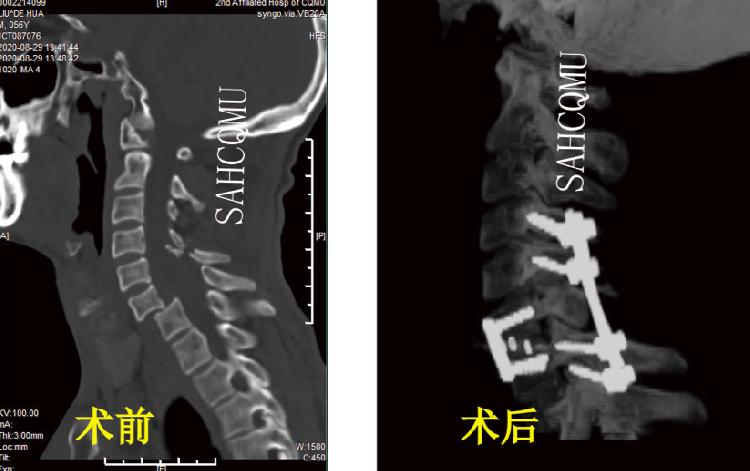

(前路C6 ACCF联合后路颈椎骨折切开复位内固定术·术前术后对比)

而当患者颈脊髓前后均有压迫或颈椎骨折脱位明显,单纯前路或者后路减压手术难以完全解除脊髓压迫或重建脊柱稳定性时,则需前后联合入路手术治疗。汪洋表示:“总而言之,原则就是哪里有压迫哪里就有‘反抗’。